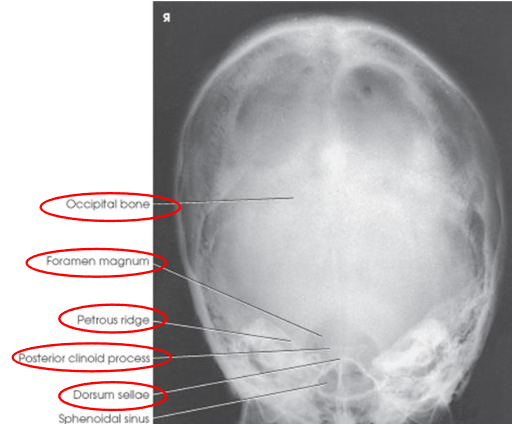

PA axial (Haas) skull image criteria

projection of dorsum sellae and posterior clinoid processes within foramen magnum

equal distance from lateral border of skull and lateral margin of foramen magnum

symmetric petrous pyramids

entire cranium